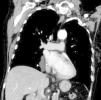

A 75-year-old woman diagnosed with a pharyngeal cancer was referred for magnetic resonance imaging of the neck and a computed tomography (CT) of the chest and upper abdomen. The enhanced CT chest demonstrated an incidental tubular cystic lesion, oriented parallel to the mediastinum, within the right pulmonary ligament, extending from the level just caudal to the right inferior pulmonary vein down to the diaphragm. This lesion measured 5.5cm×2.7cm×1.8cm and showed homogeneous density, mean attenuation value=−3.92Hounsfield Units (HU). This lesion was separated from pericardium by a layer of fat. The lesion was followed up and remained stable in size and shape for 4 years, as per the comparison with a previous CT scan. The appearance on axial, coronal and sagittal planes confirmed that the cyst was within the pulmonary ligament (Figs. 1 and 2). The cystic lesion also had no depression of the hilar structures or elevation or blurring of the diaphragm. So the non-symptomatic clinical setting alongside with the anatomical landmarks described and the lack of change in size/configuration during these years supported the diagnosis of a mesothelial cyst of the pulmonary ligament.